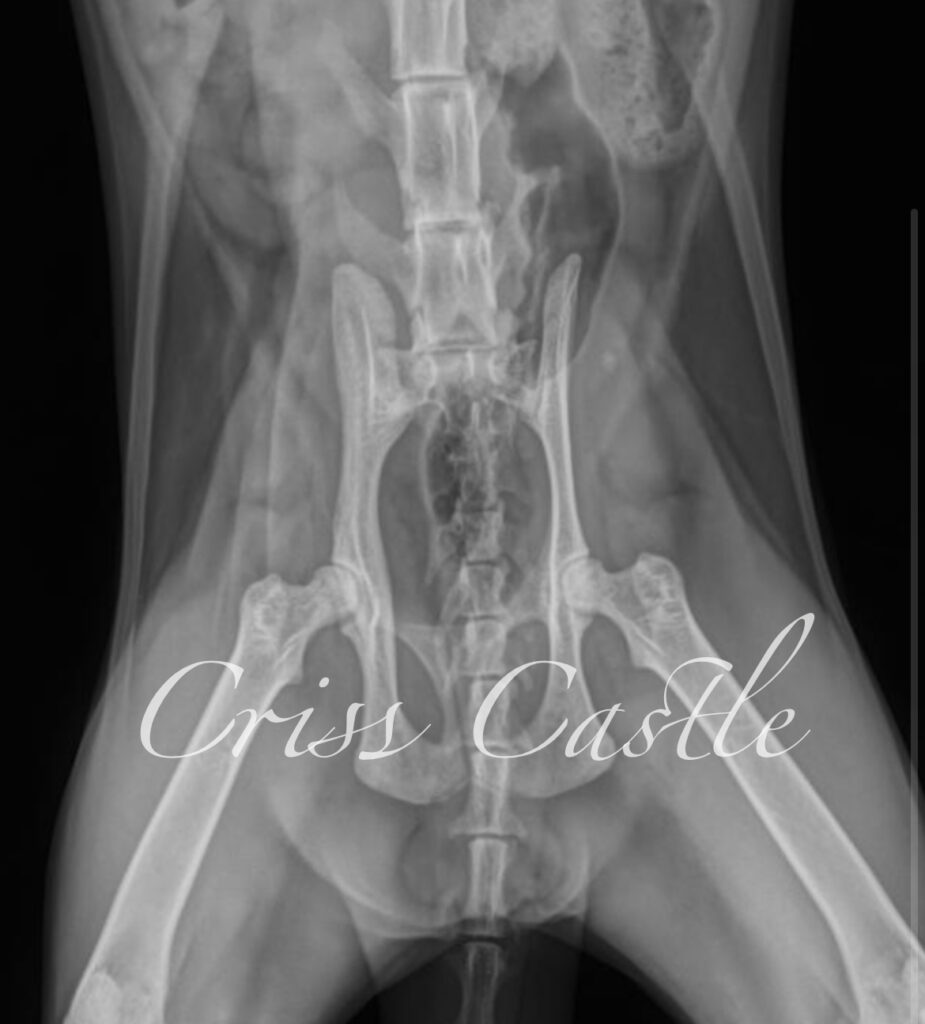

Hip X-Ray Results

Below are the current hip x-ray results for each Criss Castle breeding cat.

Note that as the cats continue to grow, this page may be updated with new results.